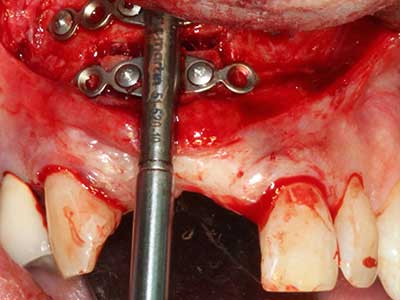

Indication: Preparation near nerves

When surgical procedures are performed on bone in the immediate vicinity of sensitive structures such as blood vessels or nerves, rotary instruments pose a significant risk of iatrogenic injury. Piezoelectric devices can be helpful for preparation of bone covers and removal of hard tissue close to nerves, particularly for exposure of nerves after iatrogenic injury but also during nerve lateralization for resective and reconstructive procedures or implant placement (Fig. 17-20). Light contact between the piezotip and the nerve does not generally result in damage but proceeding incautiously with saw-like motions or attachments where a residual bone substrate remains may cause temporary or even permanent nerve damage. However, the risk of damage is considered to be substantially lower than when using saws or milling instruments (Pereira, Gealh et al. 2014).